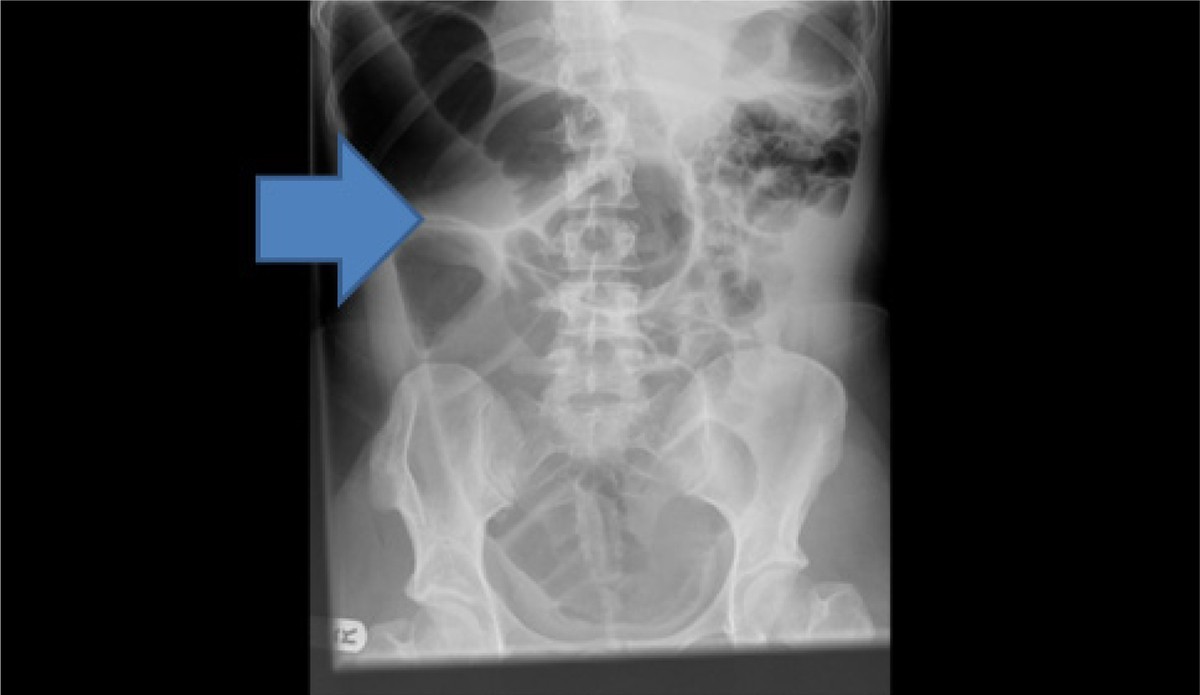

Medical Case Report Volvulus . Identify the clinical signs and symptoms of midgut volvulus, such as abdominal pain, vomiting, and abdominal distension, particularly in. Intestinal malrotation is congenital that complicates 1 in every 200 births. Thus, the timely diagnosis and. It results from abnormal fixation and rotation of the gut. Volvulus occurs when a loop of intestine twists around itself and the mesentery that supplies it, causing a. Two cases of patients with sigmoid volvulus who required emergency surgical intervention are presented.